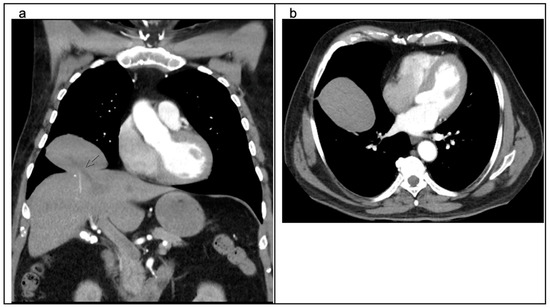

2. Detailed Case Description